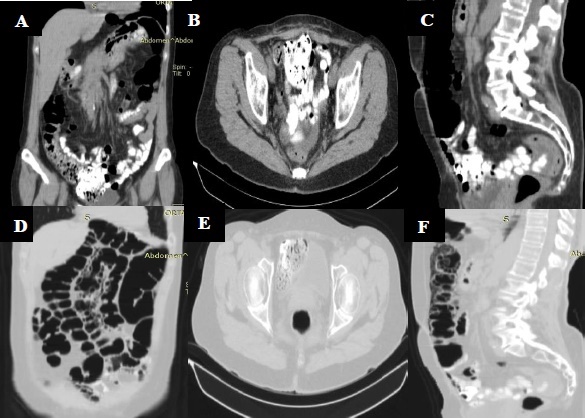

En estudio de extensión Tomografía abdominal contrastada mostró engrosamiento de la pared colónica y múltiples burbujas de aire en la submucosa, sin extravasación de medio de contraste, localizadas principalmente en las paredes del colon descendente y sigmoide (Figura 3).

Figura 3 TC con contraste: A,B,C Evidencia de neumatosis intestinal quística en colon descendente y sigmoide. En ventana pulmonar se observa burbujas de aire de paredes delgadas, sin extravasación del medio de contraste D, E y F.